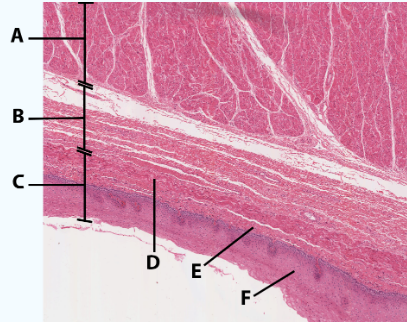

A

Muscularis

B

Submucosa

C

Mucosa

D

Muscularis mucosa

E

lamina propria

F

stratified squamous epithelial tissue

area

Esophagus